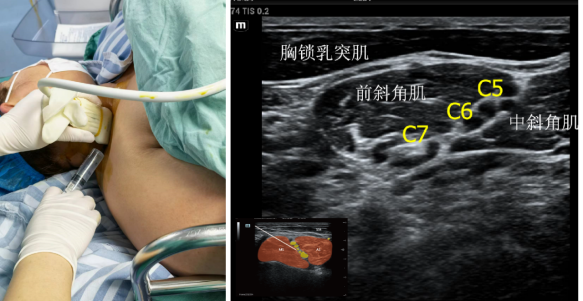

肌间沟入路臂丛神经阻滞是在第7颈椎水平进行的穿刺操作,临床实际中可能是C6到C7颈椎之间进针。为前、中斜角肌之间的3个类圆形的暗回声影。这3个类圆形结构常被误认为是臂丛的上、中、下3干。事实上,这就是C5、C6、C7这3个颈神经根的前支,它们只是组成臂丛神经3干中的2干,即上干(C5和C6组成)和中干(C7单独组成)。

超声准备:高频探头,深度3-4cm。体位:平卧位,头略微偏向健侧。或侧卧,患侧肢体位于上部。

将探头放置于颈部中央的“环状软骨水平”(环状软骨下缘平第6颈椎的下部),向外侧水平移动,从内向外依次可看见气管、甲状腺、颈总动脉、颈内静脉、胸锁乳突肌、前斜角肌、中斜角肌。此处臂丛神经根多位于前、中斜角肌之间,呈圆形或卵圆形呈串珠样分布。

穿刺方法:平面内法,一般从外侧进针,现在建议一次进针将10ml局麻药注射在臂丛神经后侧(中斜角肌侧)。因为现在的研究表明,一次注射可以大大减少膈神经麻痹的并发症,而效果和3次注射的差不多。之前注射药物追求把整个臂丛神经包裹,一般为下、中、上3个部位3次注射药液。也可以平面内法,从内侧进针,操作方法类似。但内侧进针时,需要特别注意避开膈神经,因为膈神经在前斜角表面走行,在进针经过的路径中,也更容易出现膈神经阻滞的并发症。